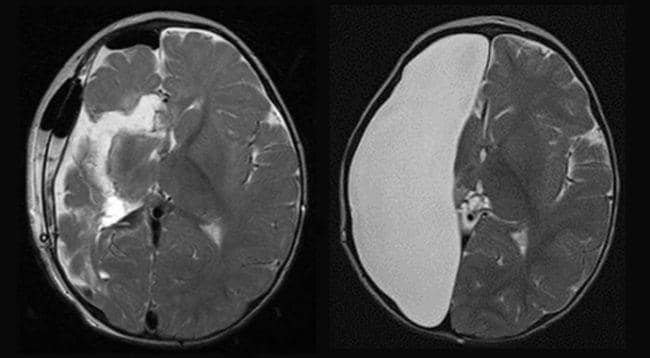

Dikenal sebagai hemispherectomy, ini adalah prosedur operasi untuk mengambil setengah bagian otak. Operasi saraf ini sangat langka dan biasanya hanya dilakukan untuk pasien yang mengalami kejang parah.

Menurut studi dari Translational Pediatrics tahun 2014, prosedur ini berhasil mengurangi kejang pada pasien hingga 90 persen. Selain itu, prosedur ini tak banyak memengaruhi kepribadian dan memori pasien.

“Pada umumnya memori, humor, dan kepribadian akan kembali seperti semula, tetapi kemampuan kognitif akan mengalami perubahan,” ujar Brandon Brock, dokter sekaligus peneliti di Foundation Physicians Group.